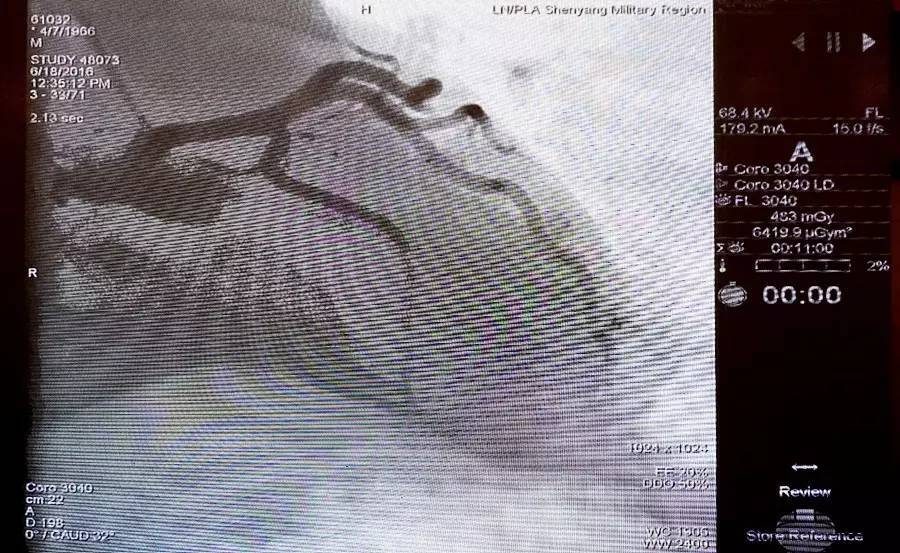

在第一场的主动脉夹层手术直播中,沈阳军区总医院王效增教授担任主要术者,陶杰、李智医生担任助手。患者为50岁男性,突发左侧胸痛2天;胸痛向后背部及腹部脐水平放散,程度剧烈,伴大汗;既往糖尿病病史6年,高血压病史2年;入院查体:T 37℃,HR 80次/分,BP 183/119 mmHg;化验检查:血肌酐 104.40 umol/L,D-二聚体 3.4 mg/L;心脏超声:主动脉硬化改变,EF 0.65;诊断:Standford B型降主动脉夹层。

术前造影